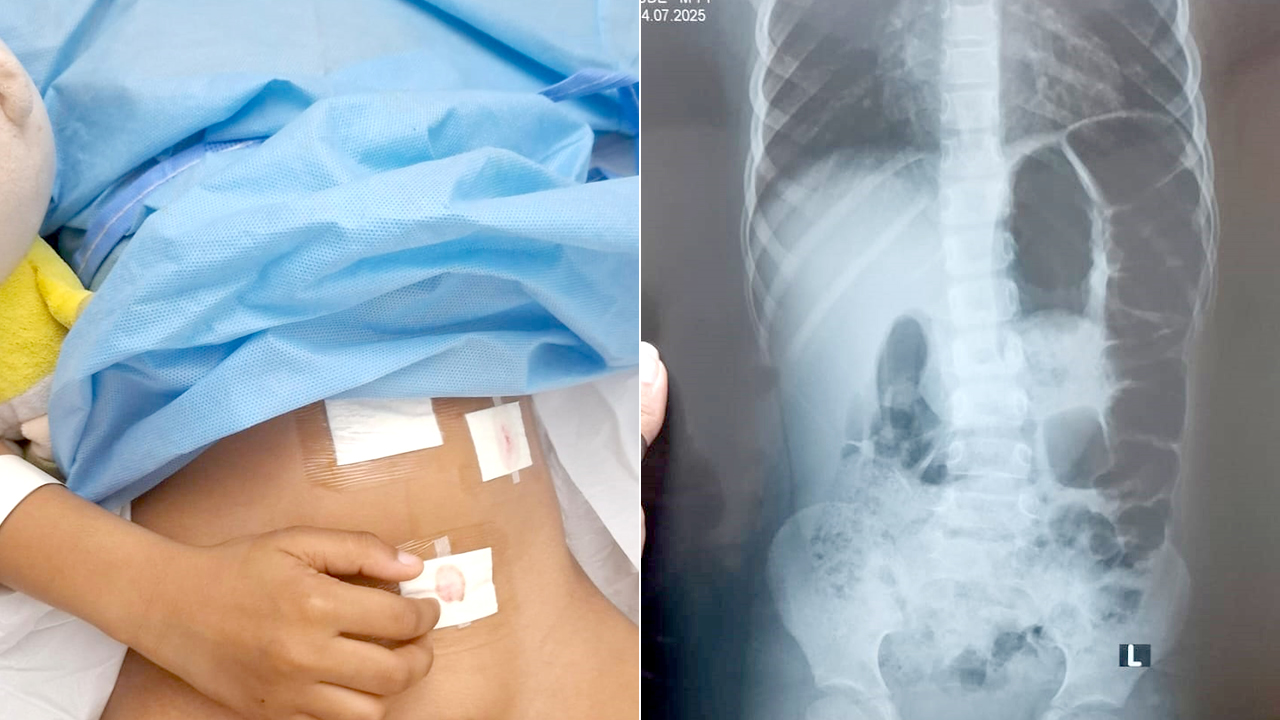

Le 14 juillet, les choses ont pris une tournure plus grave. Ce jour-là, Lyam aurait été violemment frappé dans les toilettes de l’école. L’établissement, contacté dans l’après-midi, l’informe qu’il n’y a « rien de grave », mais une visite à l’hôpital Victoria révèle une inflammation de l’appendice. L’enfant est par la suite conduit en urgence à la clinique où il subit une intervention chirurgicale immédiate. Gwendolyne est convaincue que le coup reçu a aggravé son état.